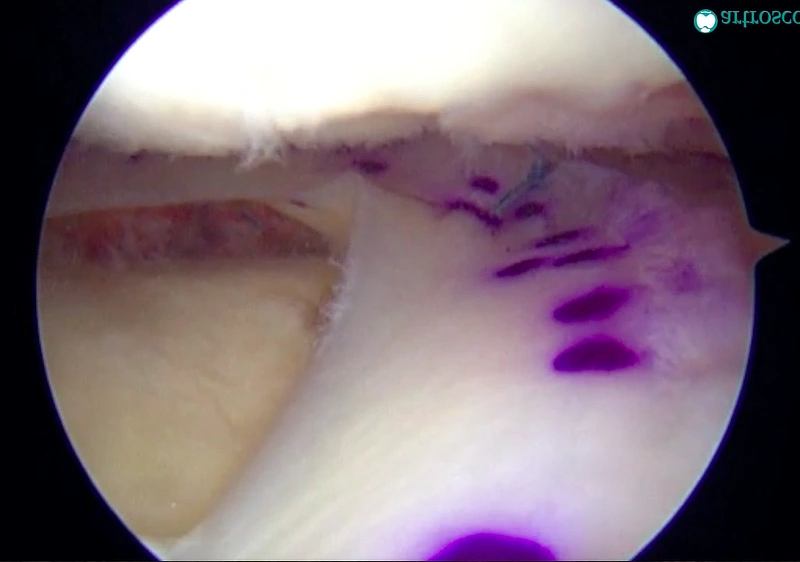

El trasplante meniscal se realiza mediante artroscopia, una técnica mínimamente invasiva. El cirujano hace pequeñas incisiones en la rodilla para insertar un artroscopio (un tubo delgado con cámara) y visualizar el interior de la articulación. Luego, se coloca el injerto meniscal en el lugar adecuado, y se fija mediante suturas o anclajes especiales.

El trasplante meniscal se realiza mediante artroscopia, una técnica mínimamente invasiva para mejores resultados y recuperación. Se observa cómo se procede a la inserción del menisco.

Detalle del proceso de fijación del injerto meniscal durante la intervención quirúrgica.

Vista artroscópica del resultado final con el menisco implantado, protegiendo la articulación y mejorando la estabilidad de la rodilla.